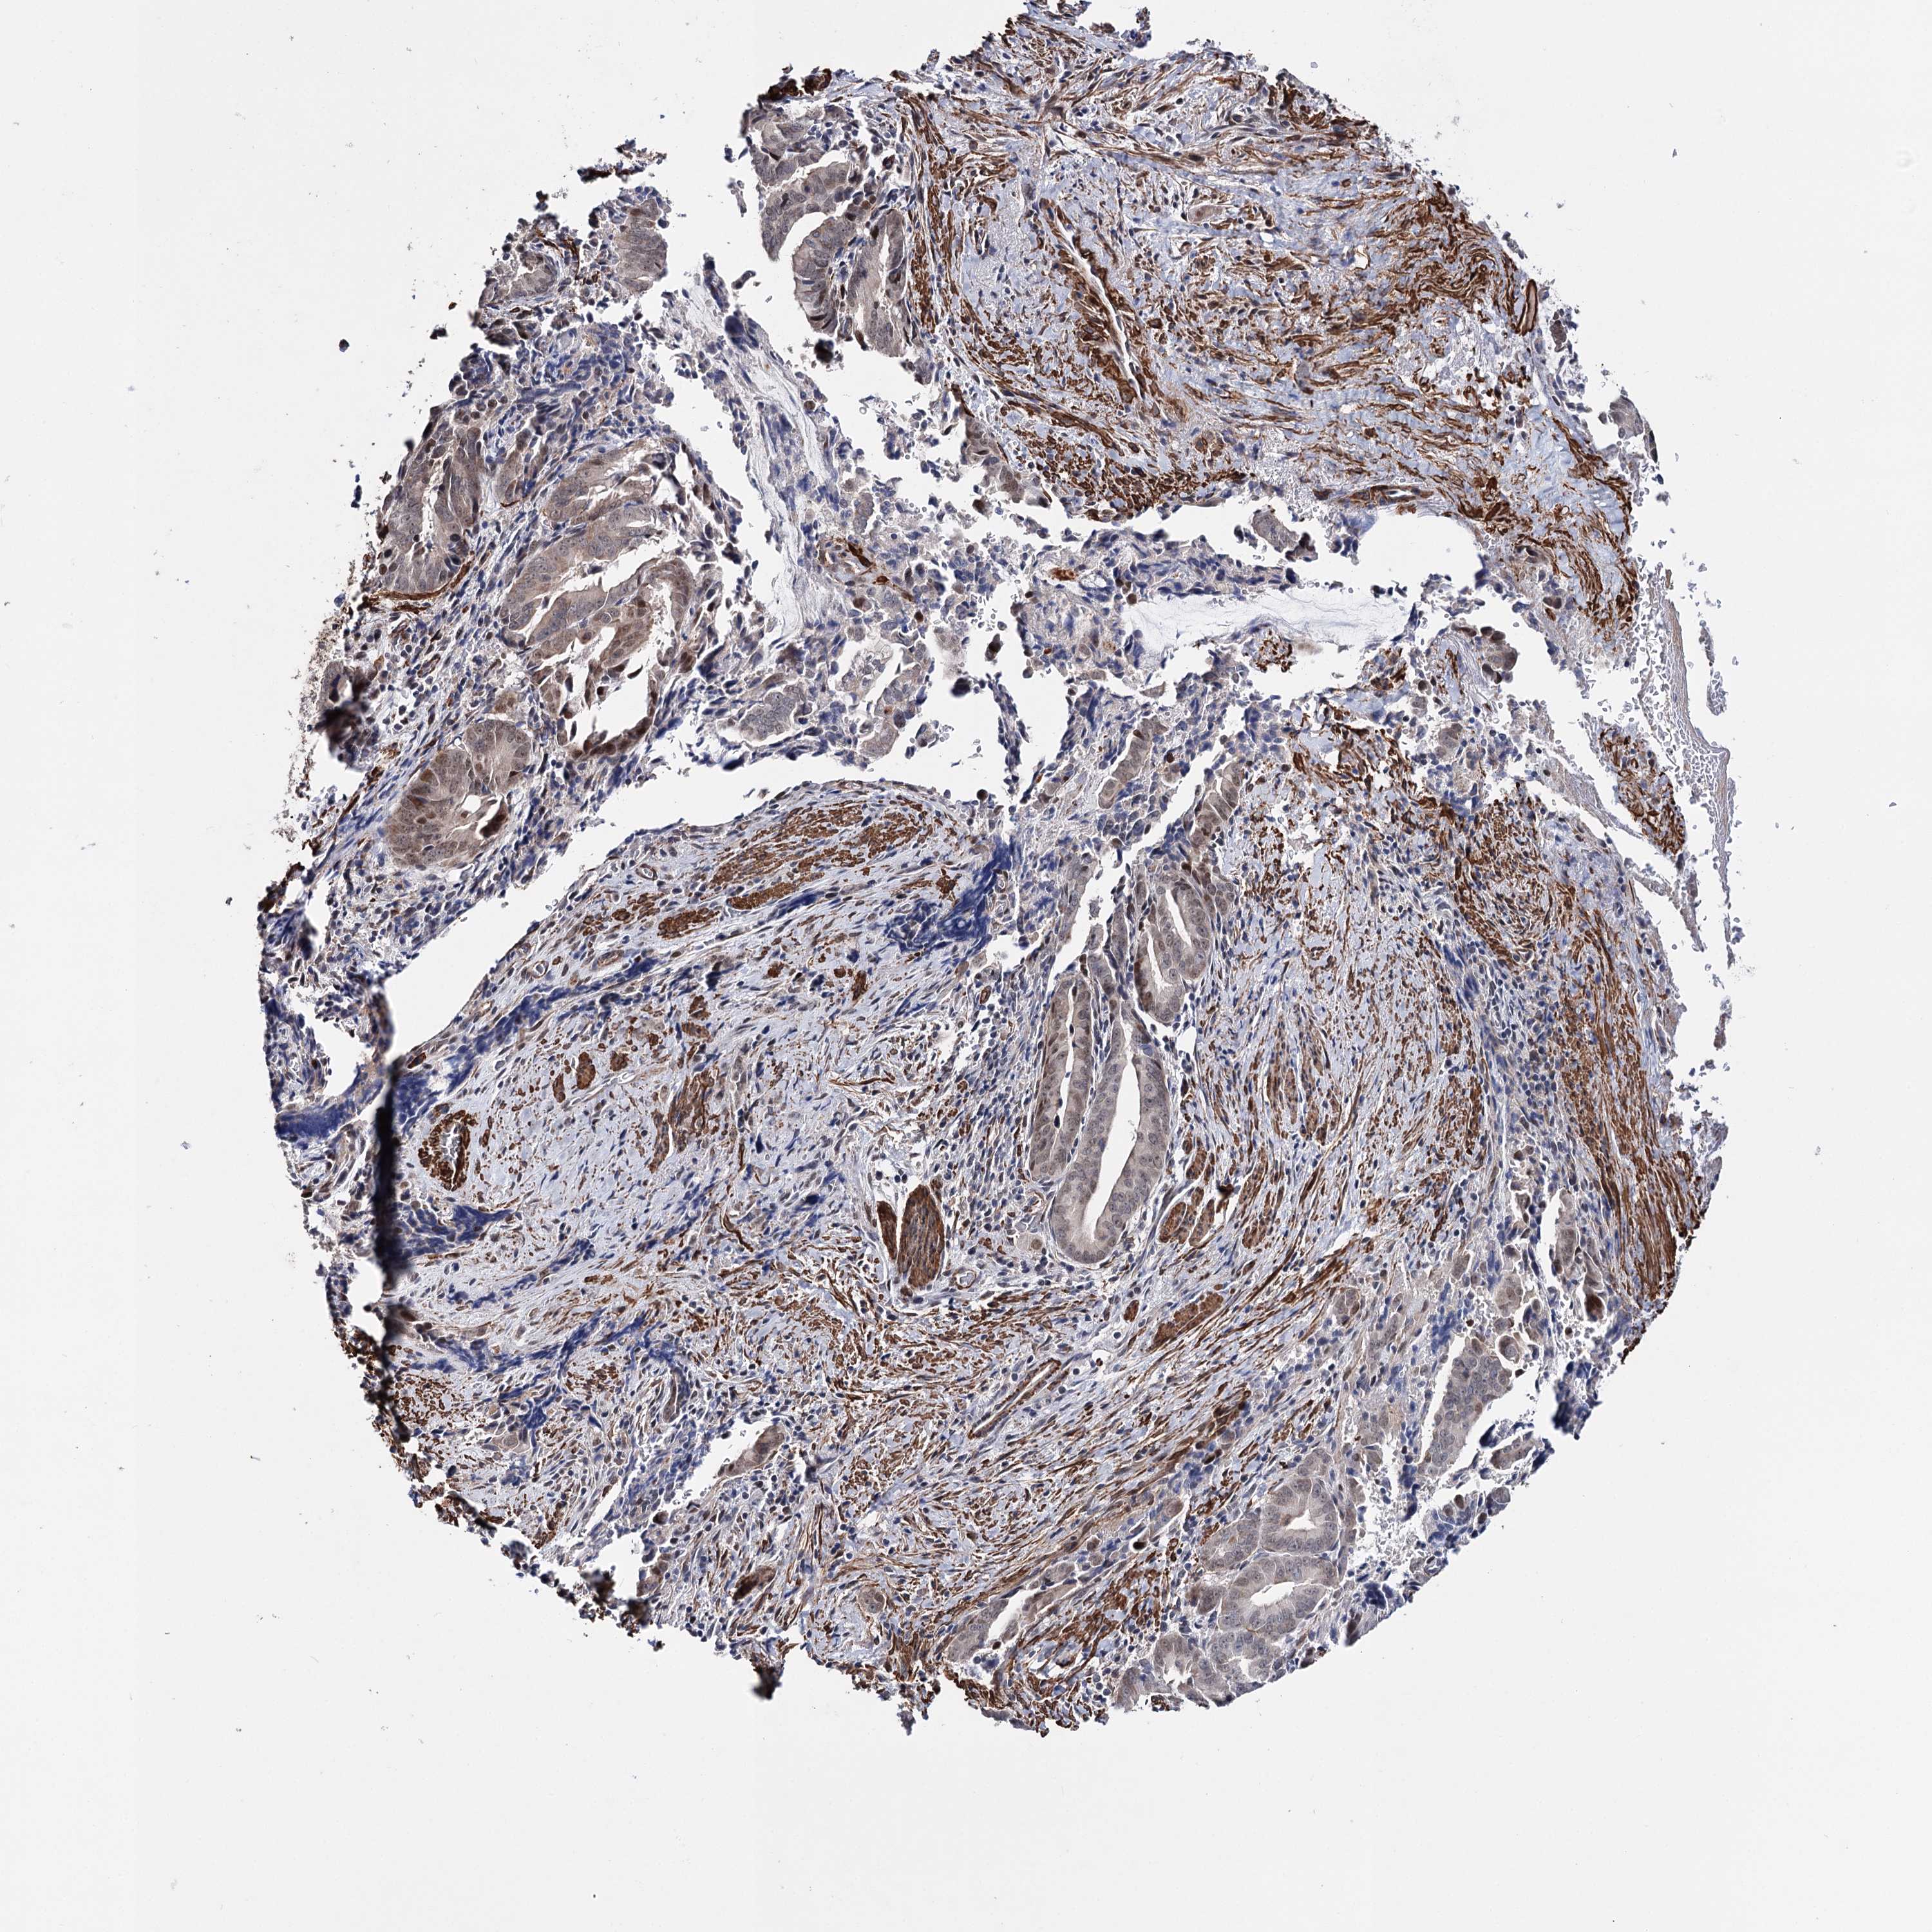

PANCREATIC CANCER - Protein expressioni

A mouse-over function shows sample information and annotation data. Click on an image to view it in a full screen mode. Samples can be filtered based on level of antibody staining by selecting one or several of the following categories: high, medium, low and not detected. The assay and annotation is described here.

Note that samples used for immunohistochemistry by the Human Protein Atlas do not correspond to samples in the TCGA dataset.

Antibody stainingi

Antibody staining in the annotated cell types in the current human tissue is reported as not detected, low, medium, or high, based on conventional immunohistochemistry profiling in selected tissues. This score is based on the combination of the staining intensity and fraction of stained cells.

Each image is clickable and will lead to virtual microscopy that enables deeper exploration of all samples and also displays staining intensity scores, fraction scores and subcellular localization as well as patient and tissue information for each sample.

Antibody HPA037786

Antibody HPA038034

Antibody HPA038867

Antibody HPA038868

Adenocarcinoma, NOS